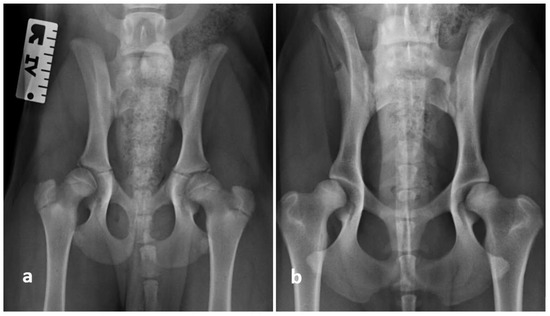

2.5. Radiographic Evaluation

3.7. Correlation between Ortolani Findings and RA/SA

4. Discussion